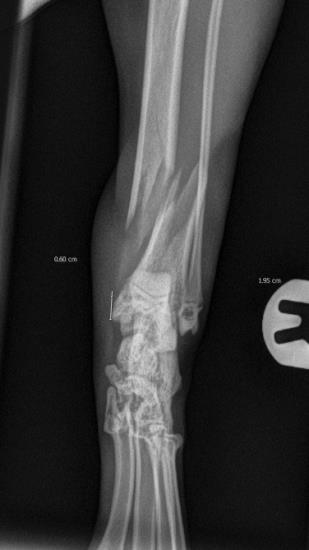

These radiographs show a distal tibial fracture in a six-month cat. Multiple fissure lines can be seen extending towards the distal tibial physis. The tibia is a common site of non-union in the cat and plate failure by bending following tibial fracture stabilisation is reported. In this case, an orthogonal plate has been applied to the cranial aspect of the tibia. This not only allows increased construct stiffness in the sagittal plane but provides for an additional screw fixation point. This can be very useful with distal fractures.